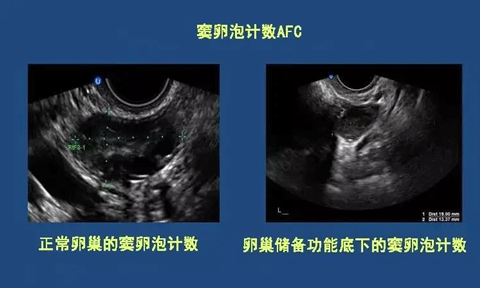

窦卵泡计数(AFC)

窦卵泡计数(AFC简介)

AFC是窦卵泡计数的缩写,是指利用B超彩超等等对卵巢的卵泡数目、大小来进行其的计数手段之一,而窦卵泡常说的是女性卵巢内直径在2-10mm的小卵泡,而通过窦卵泡计数也能够非常好的反应出卵巢储存功能等等。

什么是窦卵泡计数

女性在,最开始进行窦卵泡计数检查的时候,对于什么是窦卵泡计数都会感觉到一定的迷茫,简单的来说窦卵泡就是卵巢中成长出最为原始的3级卵泡,在阴道超声或者彩超的帮助下进行窦卵泡计数,在它们的帮助下,可以最为正确的评估与准确的计数出数量,因为女性的生育能力就是随着时间的改变而改变的,所以在医学上来说,窦卵泡计数是迄今为止最好的办法,能够在任何情况下让人知道卵巢的储存功能,以及在接受试管婴儿手术的时候也要根据这种方法来进行判断卵巢对药物反应,以增加成功率,窦卵泡计数意思就是通过这些办法计算出基础卵泡的个数,从而得到需要的结果。

窦卵泡计数大小

在进行监测的时候,窦卵泡计数大小也是有一定要求的,并不是说所有的3级卵泡都能够监测的出现,在1-2mm大小的卵泡是不能被窦卵泡计数监测到的(以及以下都被能监测),而窦卵泡计数正常大小也分为两种一种是2-9mm,一种是10mm以上的,而正常带下是在18-25mm之间。

窦卵泡计数数量

在经过窦卵泡计数准确的分析后,得出的结果并不是都曲尽人意的,在正常的数量上来说有一边卵巢在5-10个,不管是超出这个10个还是少于5个,很多时候表明了女性卵巢可能有一定的问题,如果高出10枚卵泡以上将会被怀疑为多囊卵巢,而如果低于5个的时候可能是卵巢功能低下引起的。